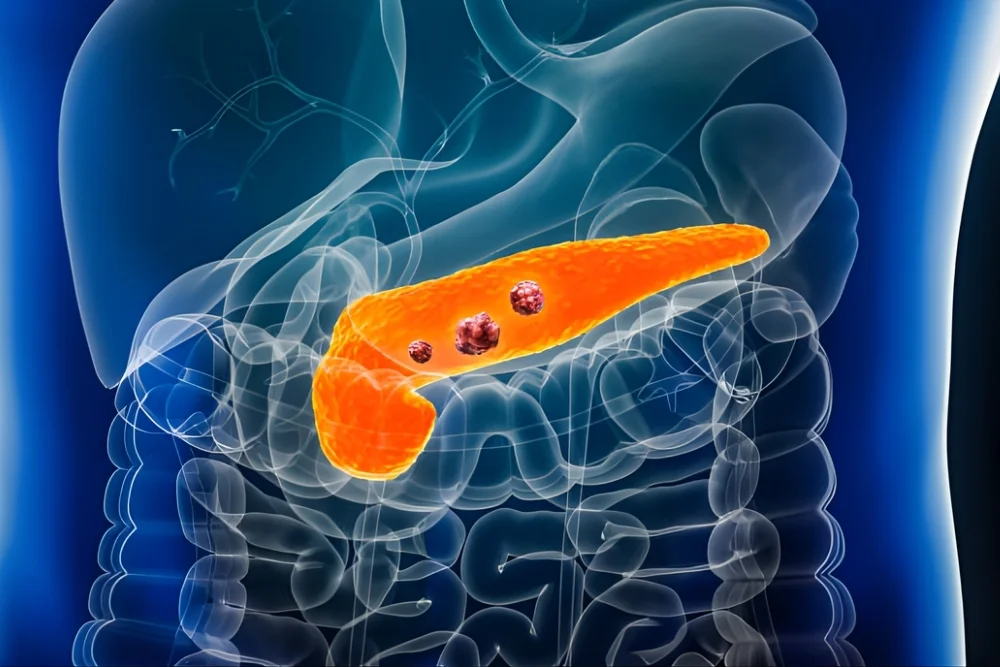

WHAT IS PANCREAS CANCER?

Pancreas cancer is a malignancy that develops when cells in the pancreas begin to grow uncontrollably. Most commonly, it starts in the exocrine cells, which produce digestive enzymes.

Over time, the tumor can invade surrounding structures, involve lymph nodes, and, if untreated, spread to the liver, lungs, or peritoneum. Early detection is key to improving outcomes, as pancreas cancer is often diagnosed at advanced stages due to subtle initial symptoms.